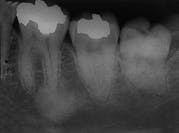

Case 2

Condensing Osteitis

1. Identify the most common location for condensing osteitis.

2. Identify the radiographic appearance of condensing osteitis.

e. irregular radiopacity

3. Identify the treatment of choice for condensing osteitis.

4. Identify the true statement concerning condensing osteitis.

e. often involves teeth #19 and #30

CASE 1: 1 = b; 2 = b; 3 = d; 4 = a

CASE 2: 1 = c; 2 = a; 3 = d; 4 = e